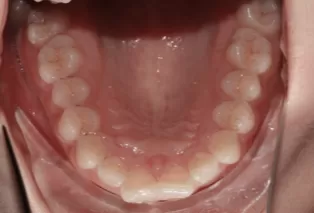

Female, 25 years old. Chief complaint: protruding and misaligned teeth, requiring orthodontic treatment.

Intraoral photos